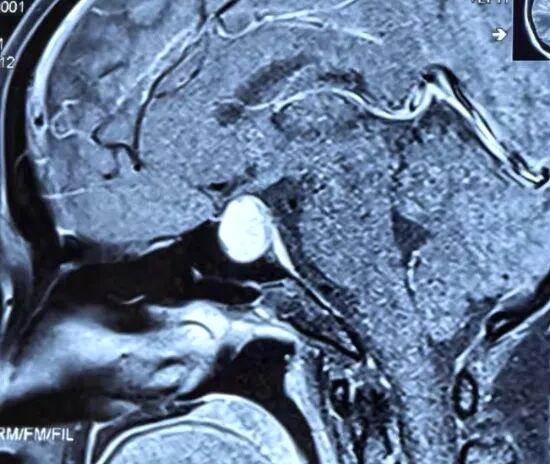

患者垂体瘤核磁共振影像

“那段时间整个人都很煎熬,头痛反复发作,月经也不规律。”张女士回忆道。多家医院初步诊断为“鞍区占位性病变”,但治疗方向未明。直至来到市二院神经外科,桑文渊主任与北京三博脑科医院张宏伟教授通过远程会诊,结合影像学和内分泌检查,确诊患者为垂体大腺瘤。考虑到肿瘤体积较大,且已引发明显临床症状,团队一致认为手术切除是最佳治疗方案。

经过周密准备,手术如期进行。张宏伟教授与桑文渊主任团队密切配合,采用经鼻蝶入路微创手术,在显微镜下完全切除肿瘤,同时完美保护了视神经和颈内动脉等重要结构。术后病理证实为垂体瘤伴卒中,与患者术前症状完全吻合。